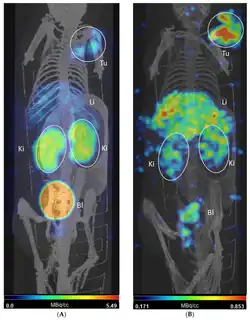

Exploration of mass separated 153Sm at MEDICIS using in vitro biological studies showed that the ability for tumors to absorb (uptake) and retain substances (retention) was improved compared to normal tissues. Animal SPECT-CT scans of mice were obtained post-injection and showed cleared activity after twenty-four hours.[33]